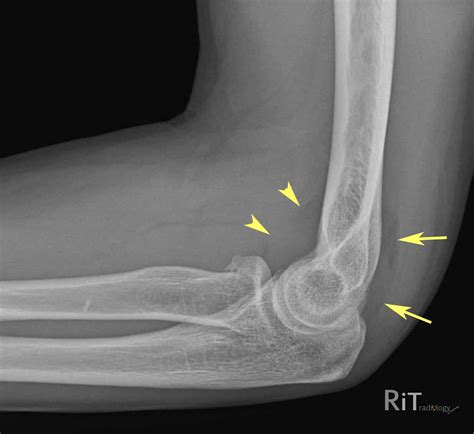

Diagnosing issues related to the elbow fat pad typically involves a combination of physical examination and imaging tests. Your healthcare provider may perform the following:

• Imaging Tests: X-rays, ultrasound, or MRI scans can provide detailed images of the elbow joint and surrounding tissues, helping to identify any abnormalities or injuries.

• elbow fat pads x ray

• positive posterior fat pad sign

• positive fat pad sign elbow

• elbow fracture fat pad sign

• elbow elevated fat pad